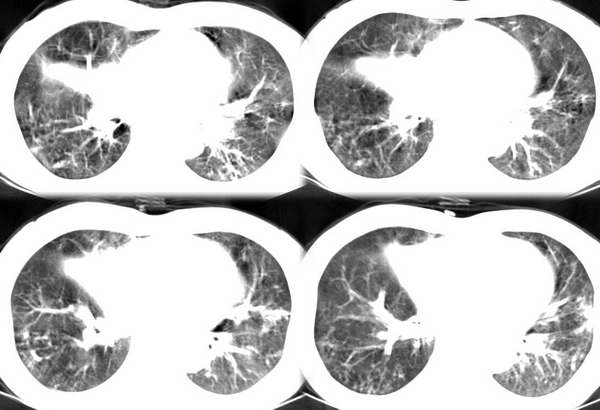

咳嗽6月低热1月!

右上肺和左下肺见有斑片状及条片状影,边缘模糊,纵隔内无肿大淋巴结,结合病史考虑肺结核可能大。

两肺纹理增粗,右上和左下肺可见肿块影,呈空泡征,分叶征。纵隔内无肿大淋巴结。考虑为肺瘤可能性大。

右肺上叶尖后段及左肺舌叶 下叶见斑片状密度不均模糊影,右中叶支气管狭窄,中叶密度增高,体积缩小.纵隔未见明确淋巴结。考虑:双肺结核伴右侧中叶不张。

三多征象,考虑双肺结核

病变多分布、多形态,再加上临床有低烧,首先考虑结核建议实验室检查进一步证实!

ct显示病灶呈多灶性分布,主要分布在双肺上叶后段,右肺中叶及左肺下叶,右肺上病灶内可见点状钙化,纵隔内示淋巴结钙化,结合病史6个月伴低热,考虑感染性病变,结核可能大.

右上叶及左下叶多发结节状、斑片状阴影。右中叶不张。支持肺结核并右中叶不张。